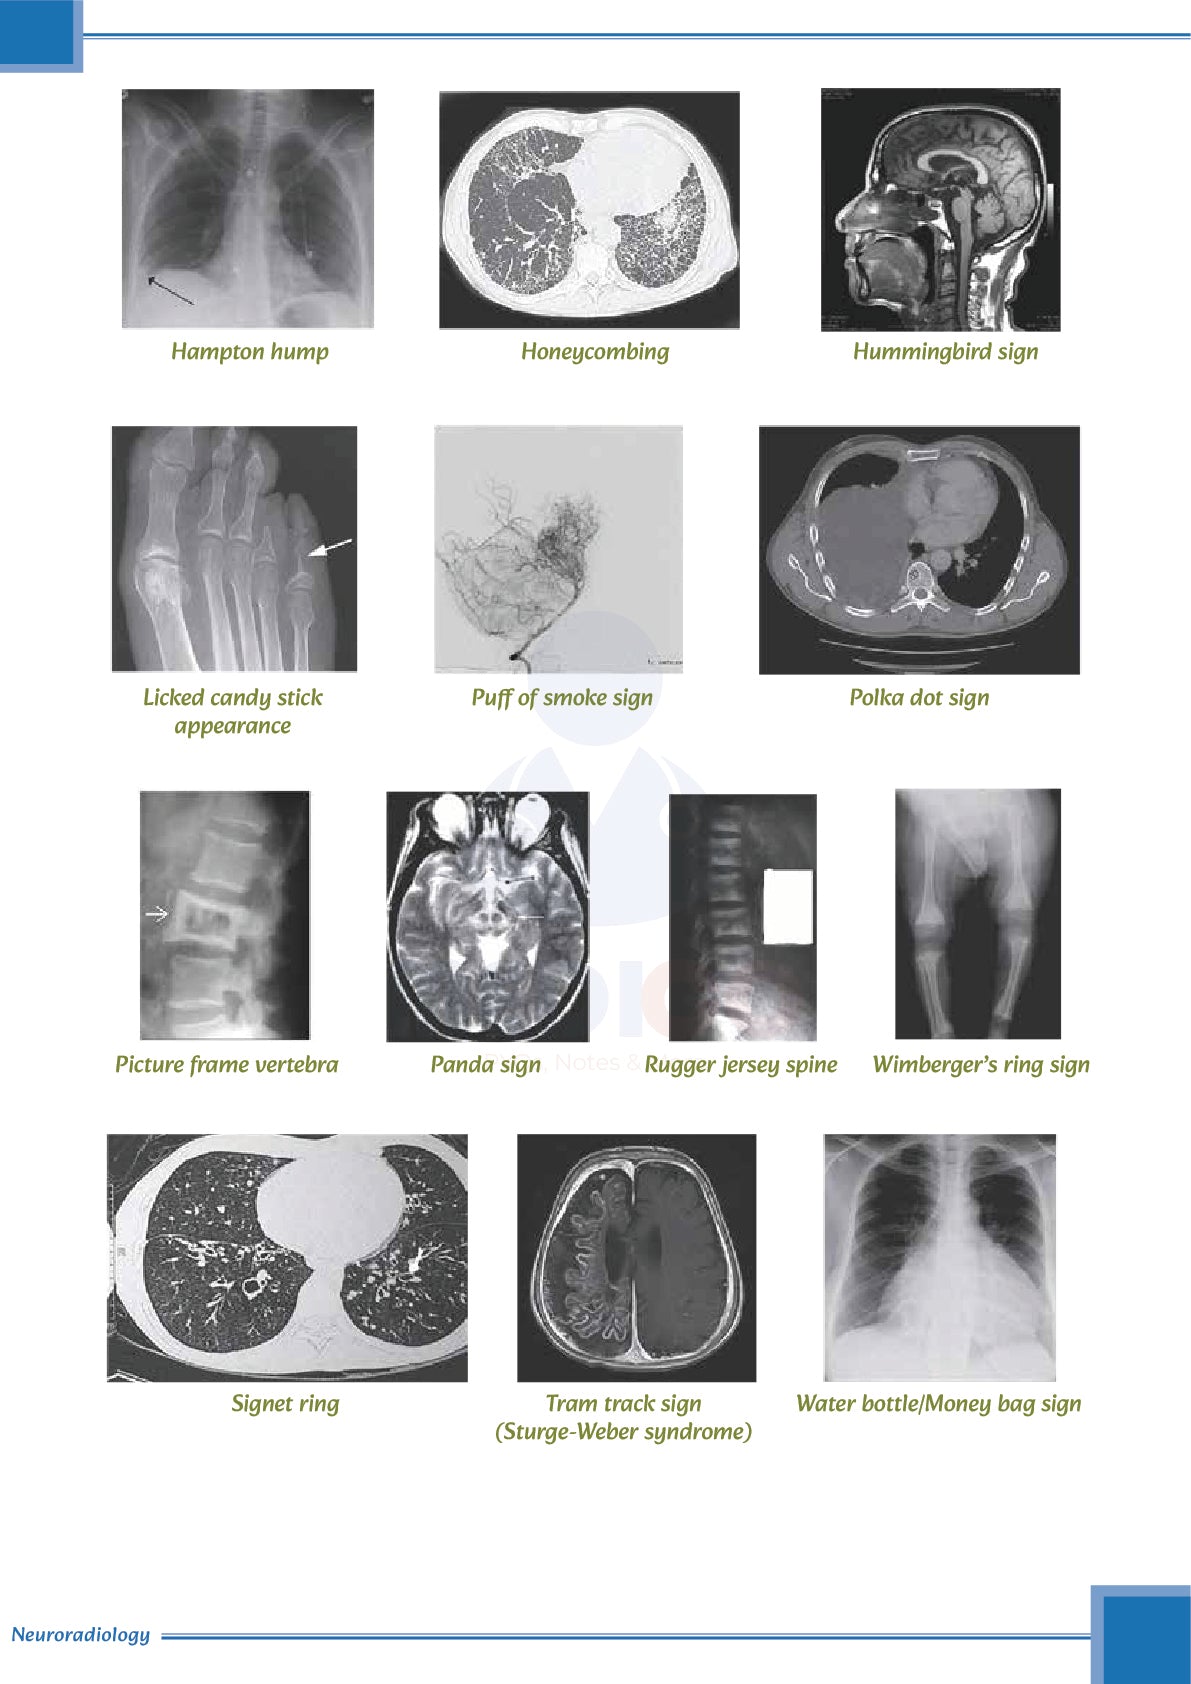

Visual Aids and Diagrams

- Includes charts, tables, and illustrations to enhance learning.